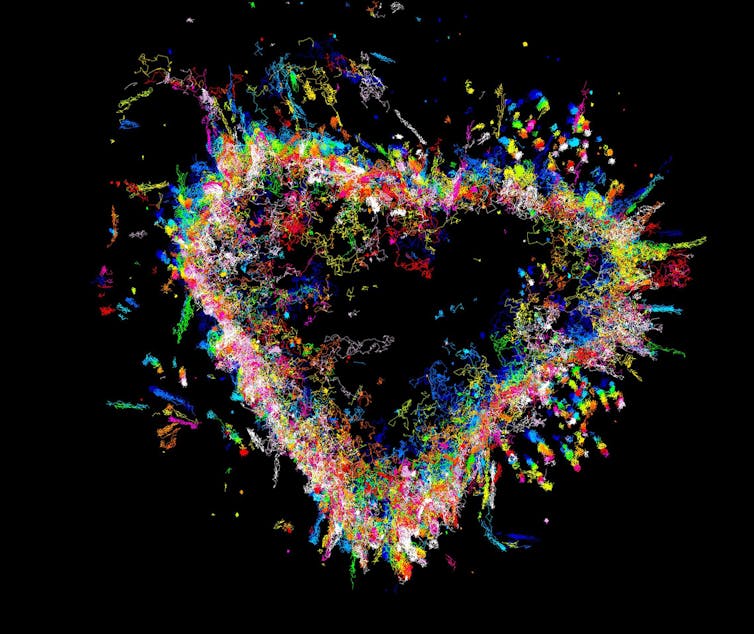

As neuroscience becomes increasingly of public interest, researchers are striving to make their findings accessible, with parallels to the pop art movement. These are MRI images of the human brain.

This image shows diffusion tensor imaging, an MRI-based neuroimaging technique, revealling the fibre tracts through the corpus callosum in a rodent brain. The corpus callosum links the brain’s left and right hemispheres to each other. The colours represent the different directions that the tracts are travelling through the brain.